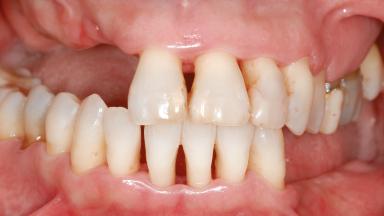

Shell Technique for Horizontal and Vertical Maxillary Bone Augmentation in a Partially Edentulous Patient with Aggressive Periodontal Disease

A 46-year-old woman was referred for treatment whose main complaints were mobility of her fixed partial dentures (right maxilla and left mandible) and periodontal bleeding during function. She also reported having taken systemic antibiotics to treat recurrent swelling in the area of the upper left molars. The patient had not seen a dentist for at least 2 years. She did not smoke and had no history of major systemic disease other than two minor orthopedic procedures some years back. The first-visit examination revealed poor plaque control, tooth mobility, periodontal disease, and a residual dentition widely associated with deep periodontal pockets.

Periodontal Phenotype Low-scalloped, thick Medium-scalloped, medium-thick High-scalloped, thin

Shape of Tooth Crowns Rectangular Triangular

Soft Tissue Anatomy Intact Defective